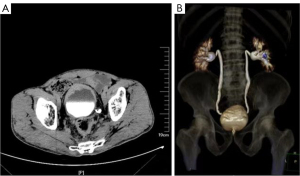

A comprehensive examination of the bladder was performed next. Computed tomography urography (CTU) demonstrated irregular thickening of the urinary bladder wall and protrusion inside the bladder lumen, particularly on the anterior wall of the bladder (Figure 2A,2B). Cystoscopy and biopsy findings revealed that the neoplastic cells were arranged in nests or single file, with inconspicuous mitotic figures and little atypia. Immunohistochemical staining showed the urothelial markers. The samples were positive for Ki67 (positive rate was 5%), P53 (focal positive), CK (AE1/AE3), GATA3, CK7, and p63. The features were comparable to those of UC; however, the Ki67 expression was found to be low.